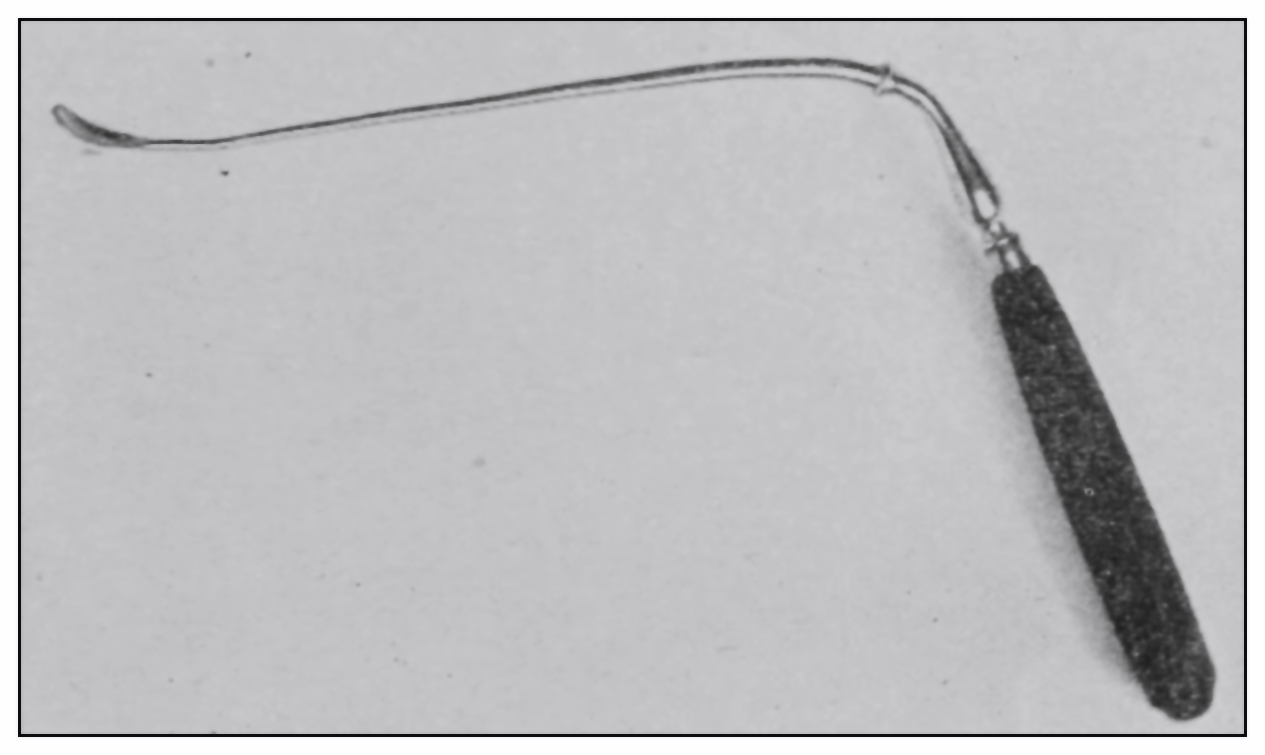

(c) The operator should observe the degree of rectal distention, the situation and number of the rectal[49] valves, their propinquity to one another when passive, and the relation of one valve to another at the time of the patient’s bearing down. Under pressure of the proctoscope if possible, or the hook if necessary, each valve should be effaced or displaced, and in regular order each of the rectal chambers should be carefully inspected. A proctoscopic mirror may be necessary for viewing the supravalvular surfaces (Fig. 18). The examination being finished:

Fig. 17.—The hook for testing the valves.